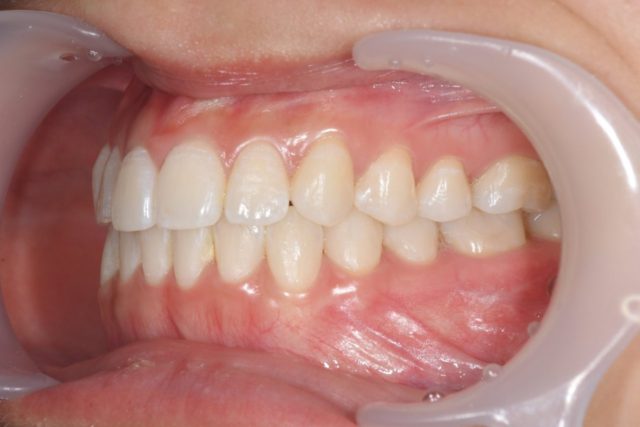

④お口を閉じたときの左側のお写真

お顔を大きく右に向いて頂き、ワイダーを引っ張って奥歯まで映しています。

左奥歯の頬側の汚れや歯茎の状態などを診ています。